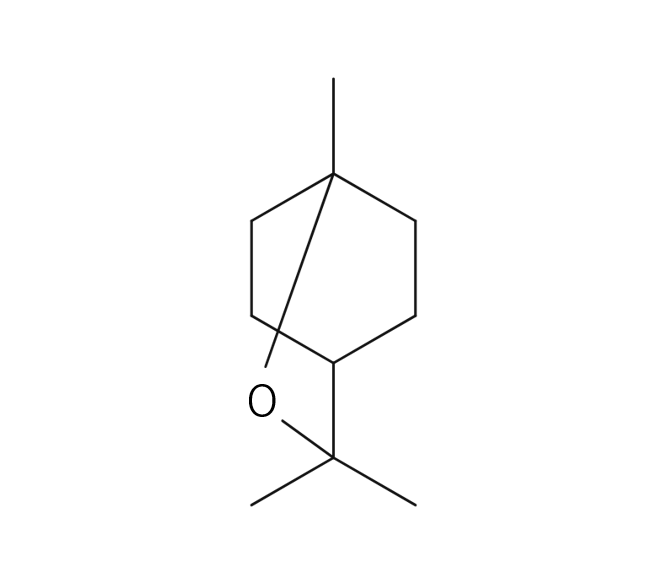

抗炎症 (Anti-inflammatory Effects)

消臭 (Deodorizing Effects)

抗マラリア (Anti-malaria Effects)

抗酸化 (Anti-oxidant Effects)

平滑筋の緊張緩和 (Smooth Muscle Relaxation)

作業能率の向上 (Work efficiency Improvement)